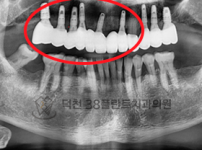

치료전후